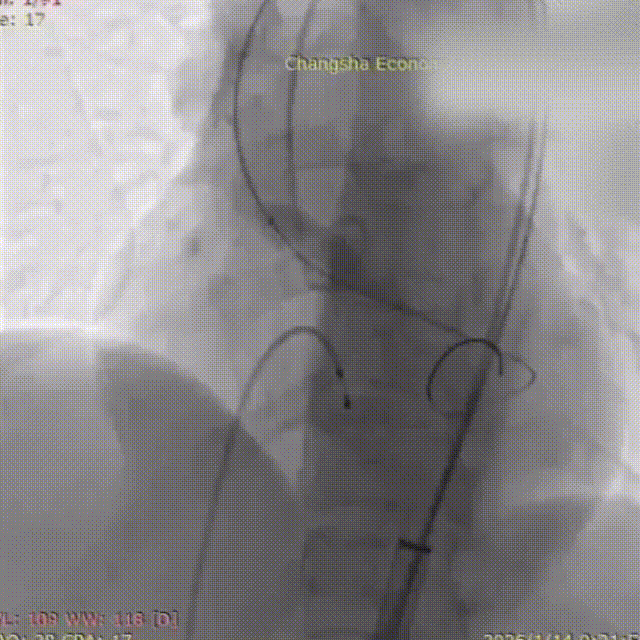

在调整血管活性药物至更稳定剂量、并做好所有应急准备后,再次进行球囊预扩张。此次扩张过程顺利,未再发生严重循环波动。造影证实球囊位置准确,无腰征,扩张过程顺利,无瓣周漏加重及冠脉阻塞征象。确定VenusA Deluxe DL 23 mm 自膨式经导管主动脉可回收瓣膜系统,经超硬导丝送瓣膜输送系统平稳通过股动脉、髂动脉及腹主动脉,无阻力送至主动脉瓣环位置。经多角度造影确认瓣膜支架标记点与主动脉瓣环、冠脉开口相对位置。最终,将瓣膜稳定释放并锚定于标准解剖位置。造影及TEE显示:人工瓣膜支架展开形态良好,无显著瓣周漏;主动脉瓣前向血流显著改善,平均压差大幅下降;左右冠状动脉显影清晰,患者血流动力学指标立时改善。

输送系统和DL23瓣膜到达释放位置定位造影

瓣膜释放至三分之二处

瓣膜开始工作,造影评估,位置良好

瓣膜完全释放,造影评估,瓣膜位置良好